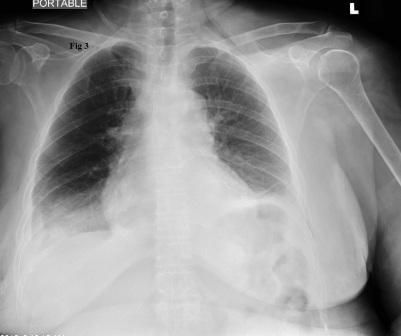

Figure 3.

A new chest radiograph showed diffuse infiltrates over bilateral lower lung fields, consistent with re-expansion pulmonary edema (REPE) (Figure 2). Noninvasive ventilation with biphasic positive airway pressure (BIPAP) was started. The patient’s symptoms improved gradually over the next 24 hours. Serial chest radiographs showed significant resolution of the previously seen bilateral infiltrates (Figure 3). However, over the following weeks, recurrent bilateral pleural effusions developed for which pleurodesis was done.